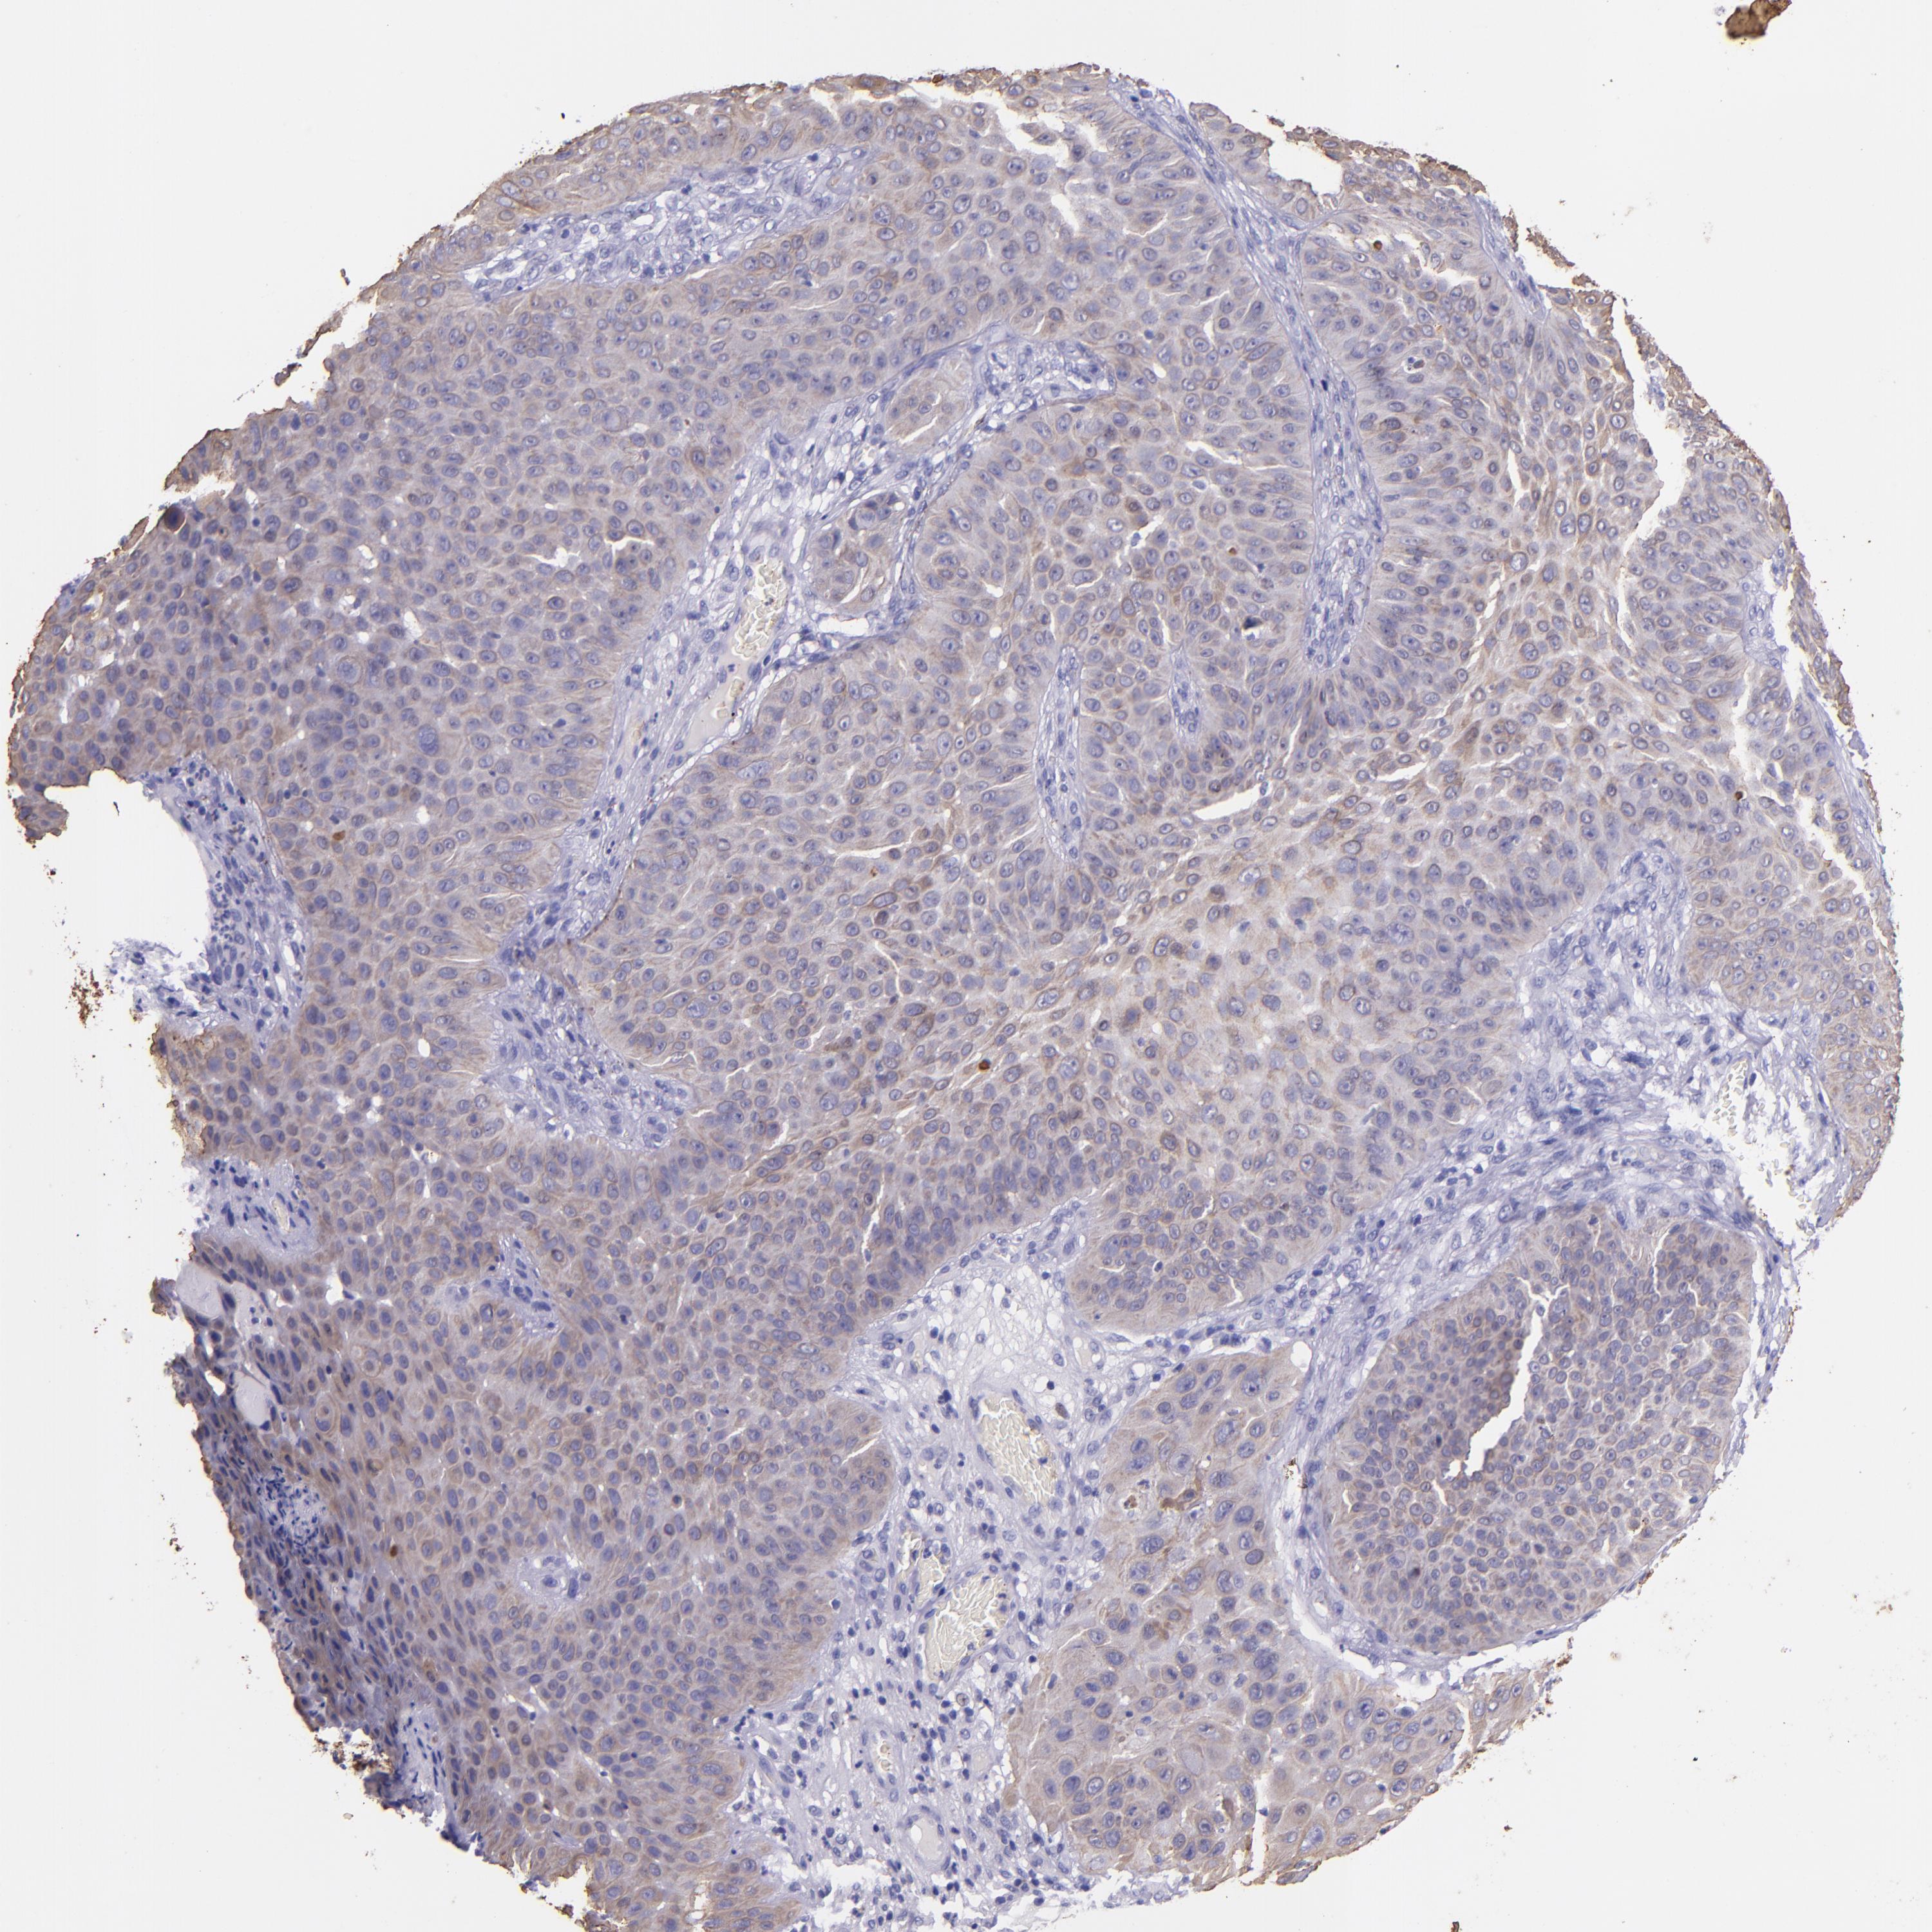

SKIN CANCER - Protein expressioni

A mouse-over function shows sample information and annotation data. Click on an image to view it in a full screen mode. Samples can be filtered based on level of antibody staining by selecting one or several of the following categories: high, medium, low and not detected. The assay and annotation is described here.

Antibody staining in the annotated cell types in the current human tissue is reported as not detected, low, medium, or high, based on conventional immunohistochemistry profiling in selected tissues. This score is based on the combination of the staining intensity and fraction of stained cells.

Each image is clickable and will lead to virtual microscopy that enables deeper exploration of all samples and also displays staining intensity scores, fraction scores and subcellular localization as well as patient and tissue information for each sample.

Antibody HPA034881

Antibody CAB002154

Basal cell carcinoma

Squamous cell carcinoma, NOS